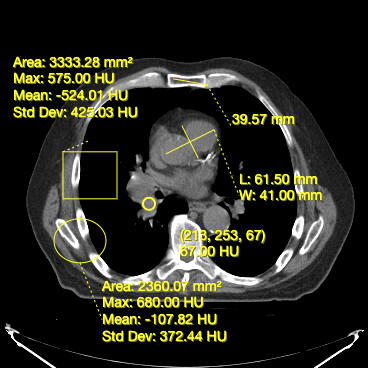

- Measuring width and length for a structure (Bidirectional Tool)

- Measuring area and statistics for a rectangular area (RectangleRoi Tool)

- Measuring volume and statistics for a ellipsoid (EllipseRoi Tool)

- Getting the underlying value for a voxel (Probe Tool)

Below, you can see a screenshot of the annotation tools that are available in Cornerstone3DTools.